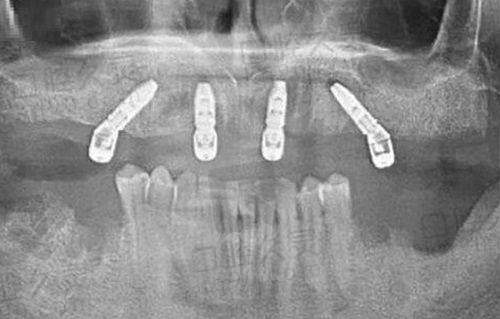

提到福州马泷齿科门诊部,不得不说它的种牙技术。马泷齿科的创办人发明创造了all - on - 4种植技术,这对于全口/半口牙缺失者来说无疑是一大福音。对于单颗牙齿缺失的情况,福州马泷齿科门诊部采用微创种植技术。这种技术创口微小,大大降低了感染风险,而且术后修复快,对高龄种牙者也十分友好。